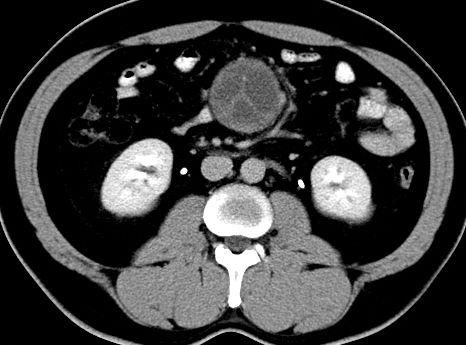

(腹腔)神经鞘瘤

男,48岁,间断性下腹不适1年。

手术探查

:距回盲部28厘米处肠系膜根部可见5*7cm左右包块,质中等硬度,活动度尚可,肝、胆、胰、脾肾未见明显异常。

病理

:(腹腔)

神经鞘瘤

,伴出血、坏死及囊性变,伴淋巴结反应性增生。

免疫组化结果

:sma(-), desmin(-), cd117(-), s-100(+++), nf(-),vimentin(+++).